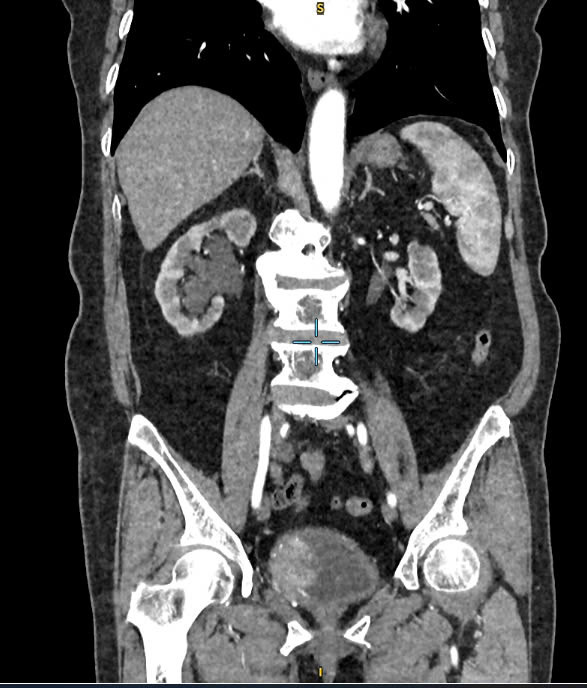

Qua khám lâm sàng và các khảo sát hình ảnh bằng soi bàng quang và chụp MSCT, các bác sĩ xác định nhiều khối u rải rác khắp bàng quang, bướu to nhất thành trái bàng quang có kích thước 3cm, xâm lấn niệu quản phải, thận phải ứ nước độ II cách miệng niệu quản trái gần 5mm, thận phải ứ nước độ II.

Dựa trên kết quả cận lâm sàng, bác sĩ chẩn đoán bệnh nhân bị bướu bàng quang trên nền bệnh tăng huyết áp, rối loạn lipid máu, đái tháo đường type 2.

| Hình ảnh tình trạng bệnh của bệnh nhân trên phim chụp |